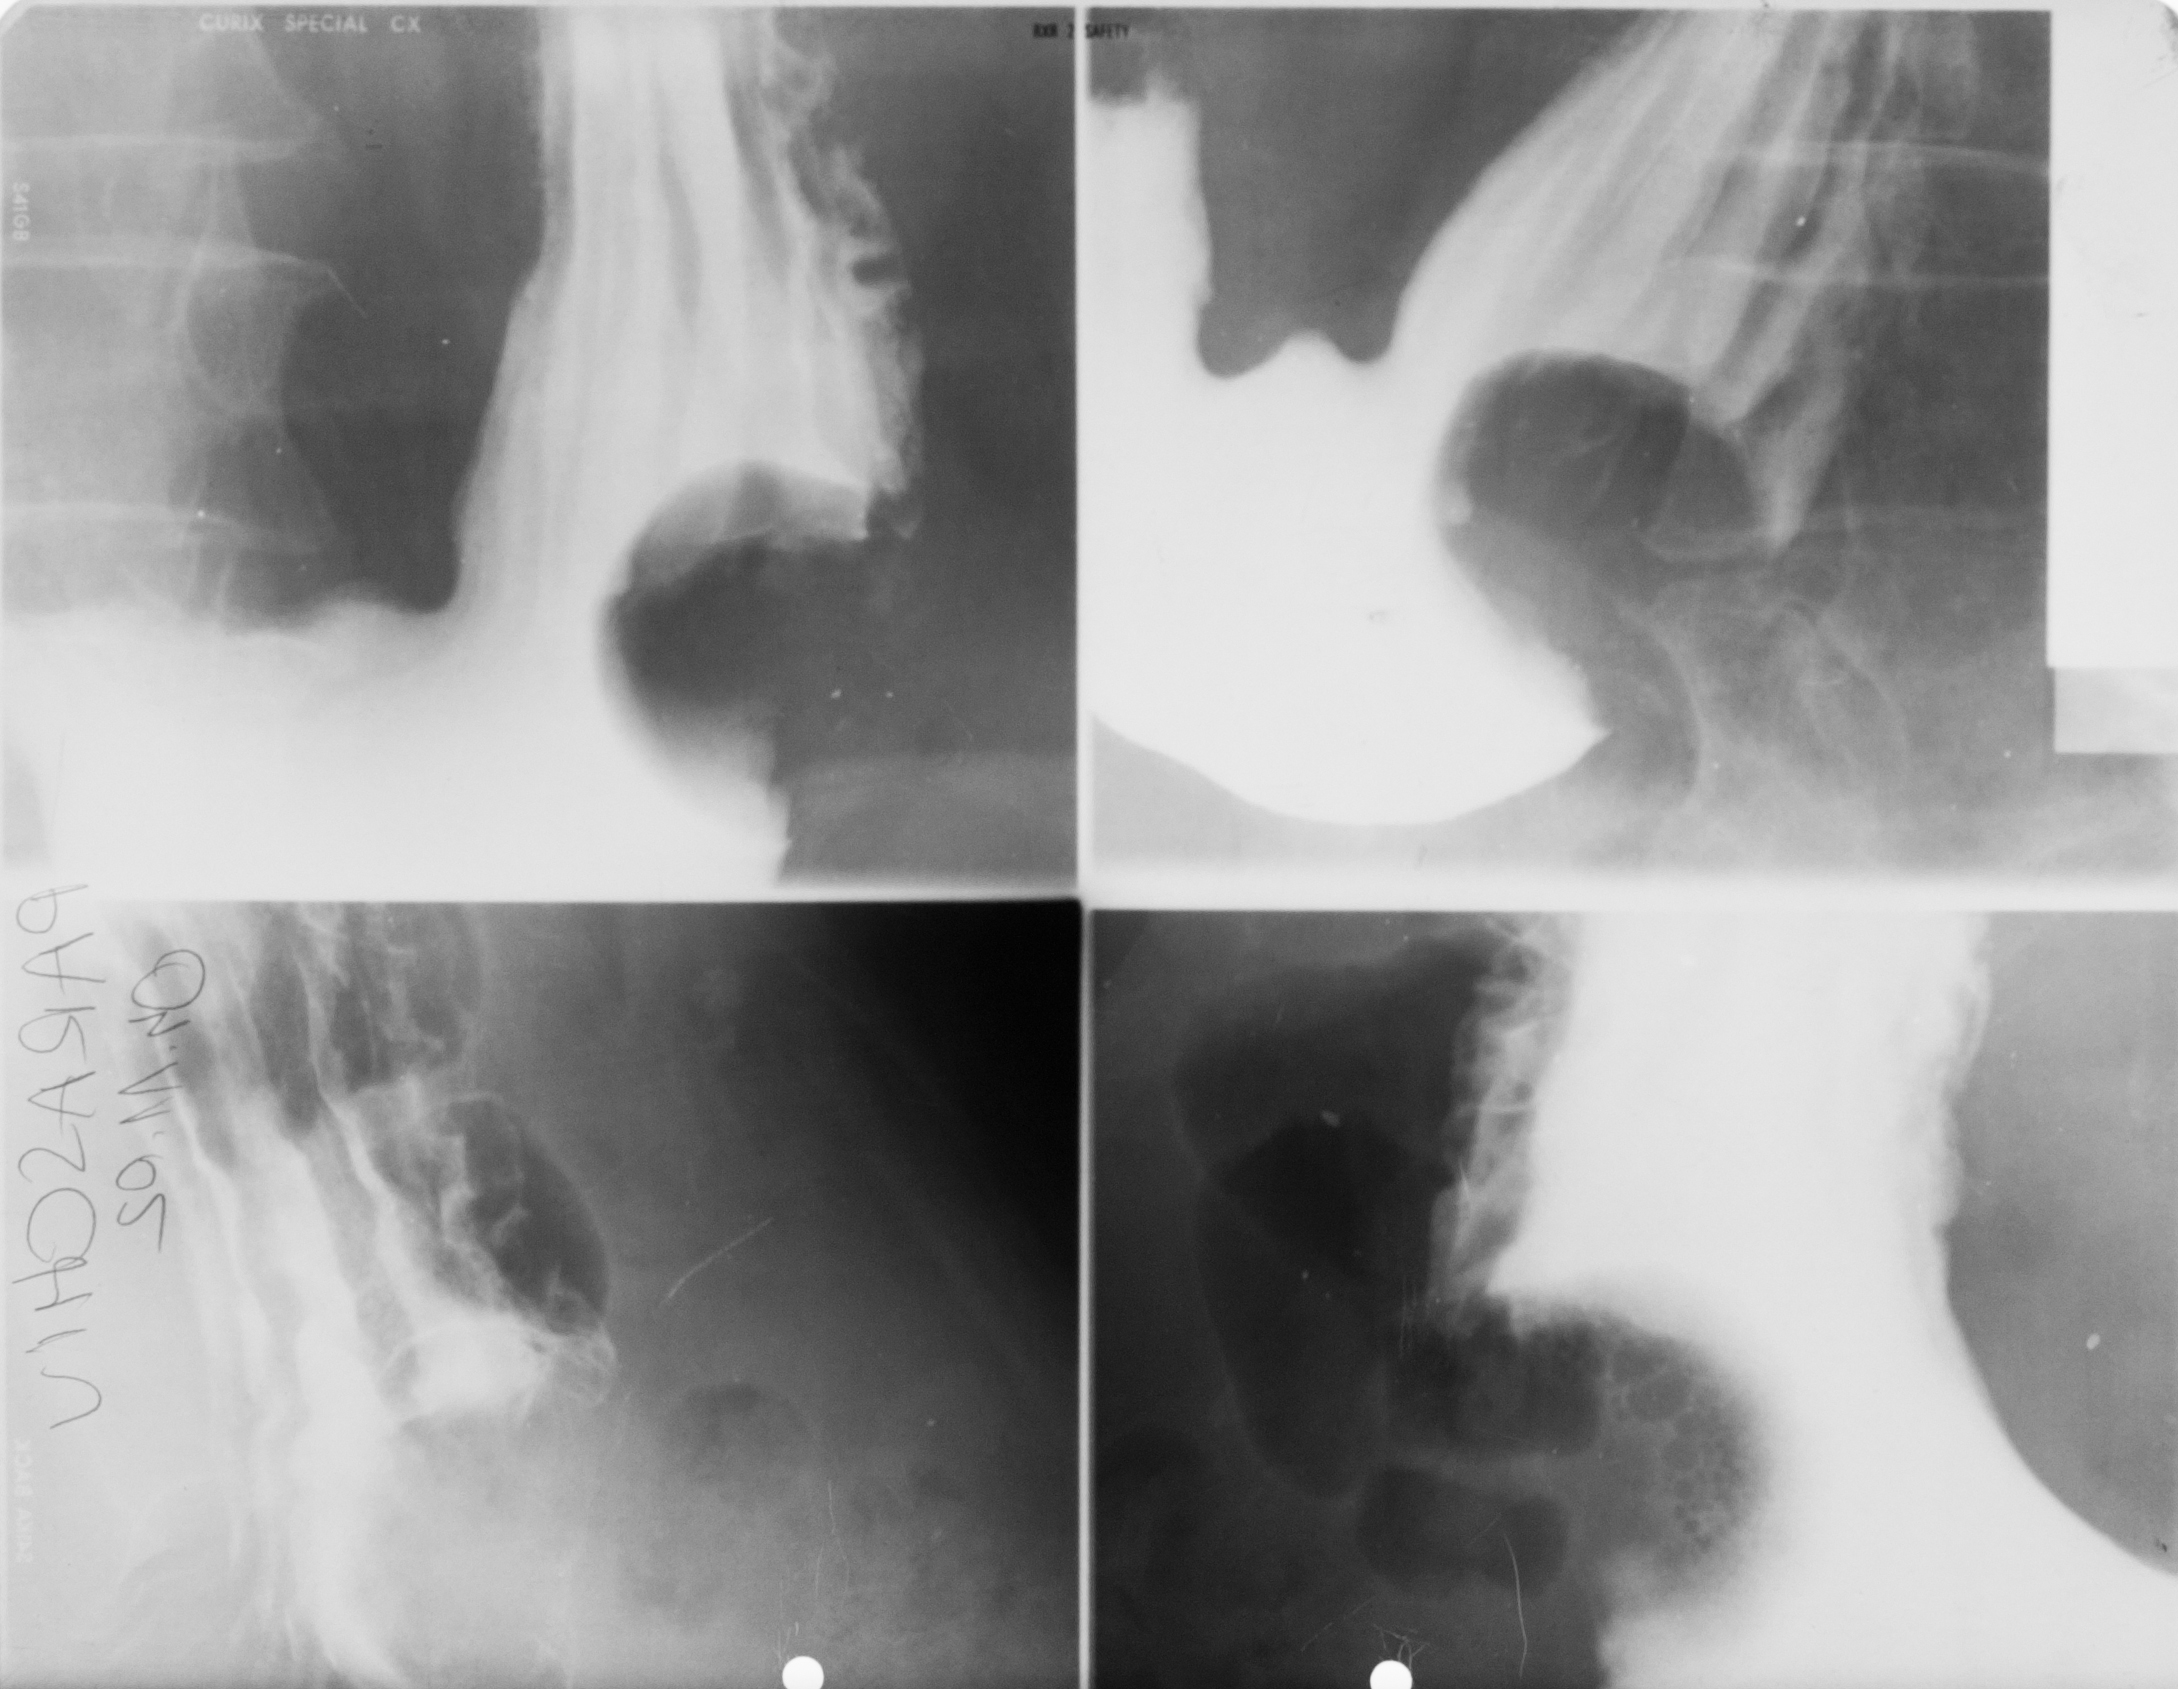

: IRIGOGRAFIE

Aspect radiologic al irigoscopiei unde recunoastem cec ascendent, flexura hepatica , transvers care este ptozat si e singura modificare care nu este neaparat patologica, flexura splenica, colon desccendent, sigmoid si rect. Absolut normal pentru persoana relativ in varsta

DEFECT DE UMPLERE (IRIGOSCOPIE/IRIGOGRAFIE)

Este rotund, bine net liniar delimitat, probabil ceva polip

DIVERTICULI (IRIGOGRAFIE)

Multiple imagini de aditie la nivelul cadrului colic

STENOZA MALIGNA = ADENOCARCINOM DE COLON

Tot irigografie cu zona de stenoza la nivelul colonului transvers, vedem coloana vertebrala si colon descendent, cu contur neregulat la extremitati, cu aspect de cotor de mar

Tot irigografie.

Zona de stenoza la nivelul colonului descendent si retrodilatatie cu aspect de pantalon de golf, proces infiltrativ la nivelul colonului. Mai putin frecvent decat adenocarcinomul

PROCES NEOPLAZIC CU STENOZĂ

Colon descendent, sigma, zona de stenoza fara mucoasa la nivelul acestei zone, proces neoplazic.

NEOPLASM

Aspect de cotor de mar cu stenoza, contur neregulat, retrodilatatii,lipsa lizereului de siguranță,deci lipsa mucoasei la acest nivel. Neoplasm

OCLUZIE LA NIVELUL INTESTINULUI SUBȚIRE

Radiografie abdominala pe gol, in etajul mijlociu, multiple imagini hidroaerice, cu ax transversal hidroaeric, cu ax transversal mai mare decat axul craniocaudal. Nivele hidroaerice de tip intestin subtire

OCLUZIE(situată mai jos) SAU ILEUS DINAMIC

Nivele hidroaerice de tip intestine gros, cu ax mare vertical si nivele hidroaerice de tip intestin subtire, posibil ocluzia este undeva mai jos sau sa fie Ileos dinamic

Imagine hidroaerica tipica de intestine gros, ax mare vertical, ax mare vertical mai mare decat ax orizontal, se vad haustrele deci clar se poate recunoaste colonul

PNEUMOPERITONEU

Imagine hipertransparenta, semilunara situate sub cupola diafragmatica dreapta